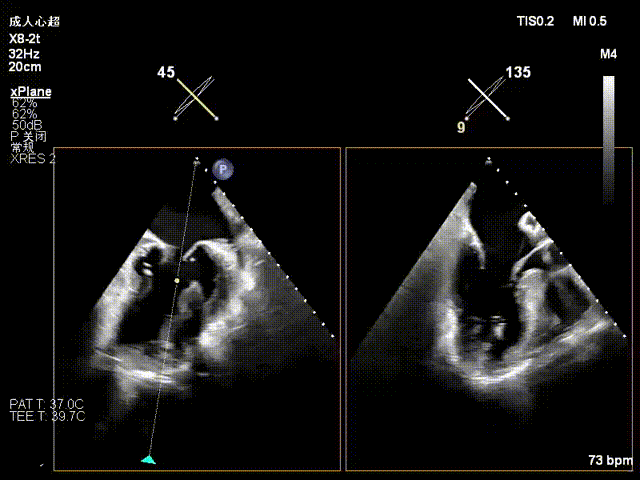

一夹后图像,残余反流位于2区

跨瓣器避过一区夹子,再次跨瓣进入左房

16F鞘送入左房

在左房打开上夹,调整好位置角度后在左室打开下夹

确认夹子位于反流区